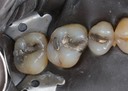

Mark Chun #13,14,15 pre-op

Mark Chun #13,14,15 amalgam removal

Mark Chun #13,14,15 prep